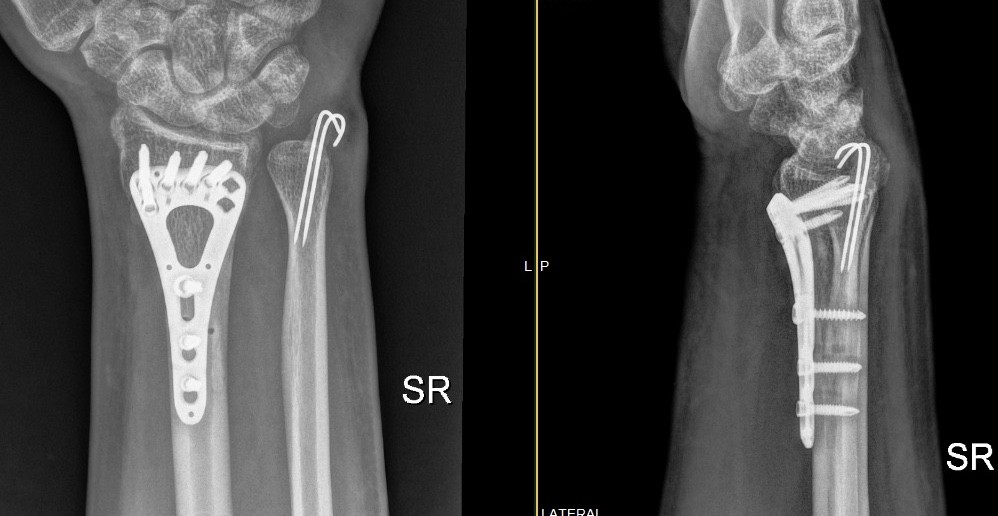

X-rays: To detect fractures or dislocations

Repair of fractures, dislocations, tendons, or ligaments

Fractures: Broken bones in fingers, metacarpals, or wrist

Postoperative Rehabilitation: Vital for regaining full function